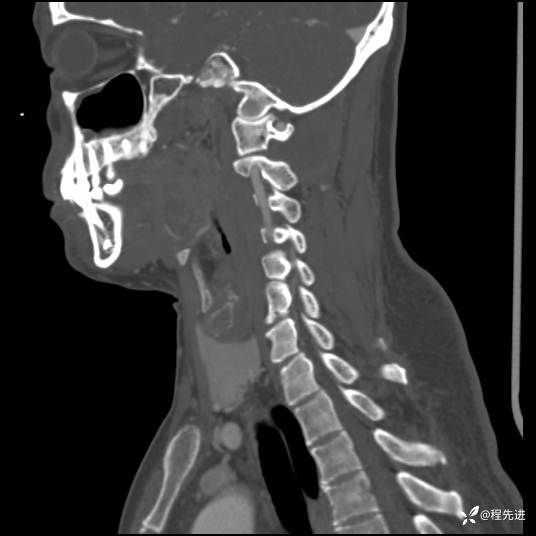

CT平扫+增强:

现病史:患者3个月前低头工作后感颈部疼痛,隐痛,活动颈部后稍好转,无上肢麻木不适,无肢体活动障碍,无头晕头痛,3个月来疼痛反复发作

患者性别:男

患者年龄:43岁

主诉:颈部疼痛3个月